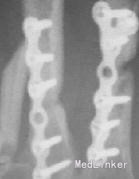

入院诊断左手损伤,左第2~5掌骨开放性粉碎性骨折,左第2~5指伸肌撕脱损伤,左手背软组织挫裂伤伴缺损,左中、小指指深屈肌腱断裂,左环指指深屈肌腱撕脱损伤,左手骨间肌、蚓状肌断裂、挫裂伤,左手指掌侧总神经、指背侧总神经及指神经断裂,左手指掌指总动静脉、掌浅弓、掌深弓断裂,左手掌软组织挫裂伤,左大小鱼际肌部分断裂,左桡骨下段横形骨折,左肘部软组织损伤。入院后给予急诊清创固定1周后左小指、环指缺血坏死,再次手术行左环、小指切除,左第5掌骨切除、左第4掌骨残端修整、左桡骨下端切开复位固定术,左第2、3掌骨骨折端术后5个月无愈合迹象。术后X线片提示:骨折断端存在间隙,骨痂很少或无,断端分离,髓腔封闭,骨质疏松,无骨小梁形成,符合骨折不愈合诊断。

该患者骨折不愈合处获得完全骨性愈合,临床愈合时间2个月。治疗过程中未出现针孔及深部感染。